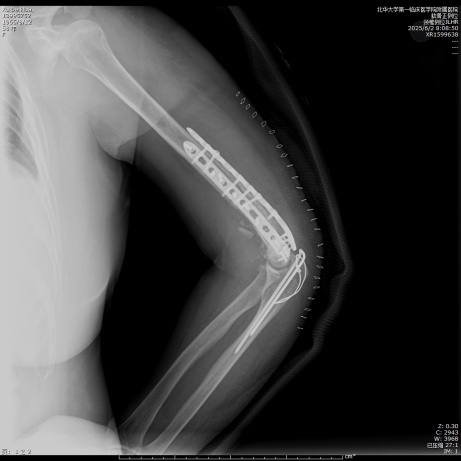

患者徐女士,58岁,因“高处坠落伤致右上臂肿痛、畸形、活动受限2小时”入院。患者于2小时前在家中不慎从3 m高的梯子上不慎掉落摔倒伤及右上臂,即感右上臂剧烈疼痛伴明显活动受限,遂至我院就诊,查体见右上肢三角巾悬吊中,皮肤感觉正常,右上臂中下段及前臂明显肿胀、屈曲畸形,肌张力明显增高,肘关节前侧及内侧皮肤可见张力性水疱,未见明显皮下瘀斑,触痛明显,轴向叩击痛(+),右肩、肘关节活动度因疼痛不能查及,肘后三角关系正常,腕关节及各手指活动度正常,桡动脉搏动可触及,末梢血运良好。急诊行右肱骨X线片检查,提示:右侧肱骨干及肱骨外侧髁可见骨折线影。遂以“右侧肱骨干骨折”收入院。因肱骨干中下1/3段后外侧骨表面有桡神经沟,为防止骨折端不稳损伤刺破神经及肱动脉,故给予右上肢石膏外固定,止痛、消肿等对症治疗,嘱其抬高患肢,抓绕手指。入院后完善右肱骨CT (平扫,三维重建)检查(见图1),提示:右肱骨干、肱骨小头、肱骨滑车、肱骨外侧髁、内侧髁、桡骨头可见骨质多发断裂,断端对位对线欠佳,局部成角,断端分离移位,周围组织增厚,尺骨近段未见异常,右肘关节腔内见片状液体密度影。最终临床诊断为:右侧肱骨干骨折、肱骨滑车骨折、肱骨小头骨折、肱骨内外髁骨折、桡骨头骨折。完善术前相关检查,未见明显异常及相关手术禁忌症,待患肢肿胀情况明显消退后,根据术前影像学资料及患肢的皮肤条件(右肘前侧及内侧皮肤因张力性水疱导致皮肤破溃),最终手术方案选择在插管全麻下行后侧经尺骨鹰嘴截骨入路切开复位双钢板内固定术。

Figure 1. Preoperative CT scan of the elbow joint with plain imaging and 3D reconstruction

1. 术前肘关节CT平扫及三维重建